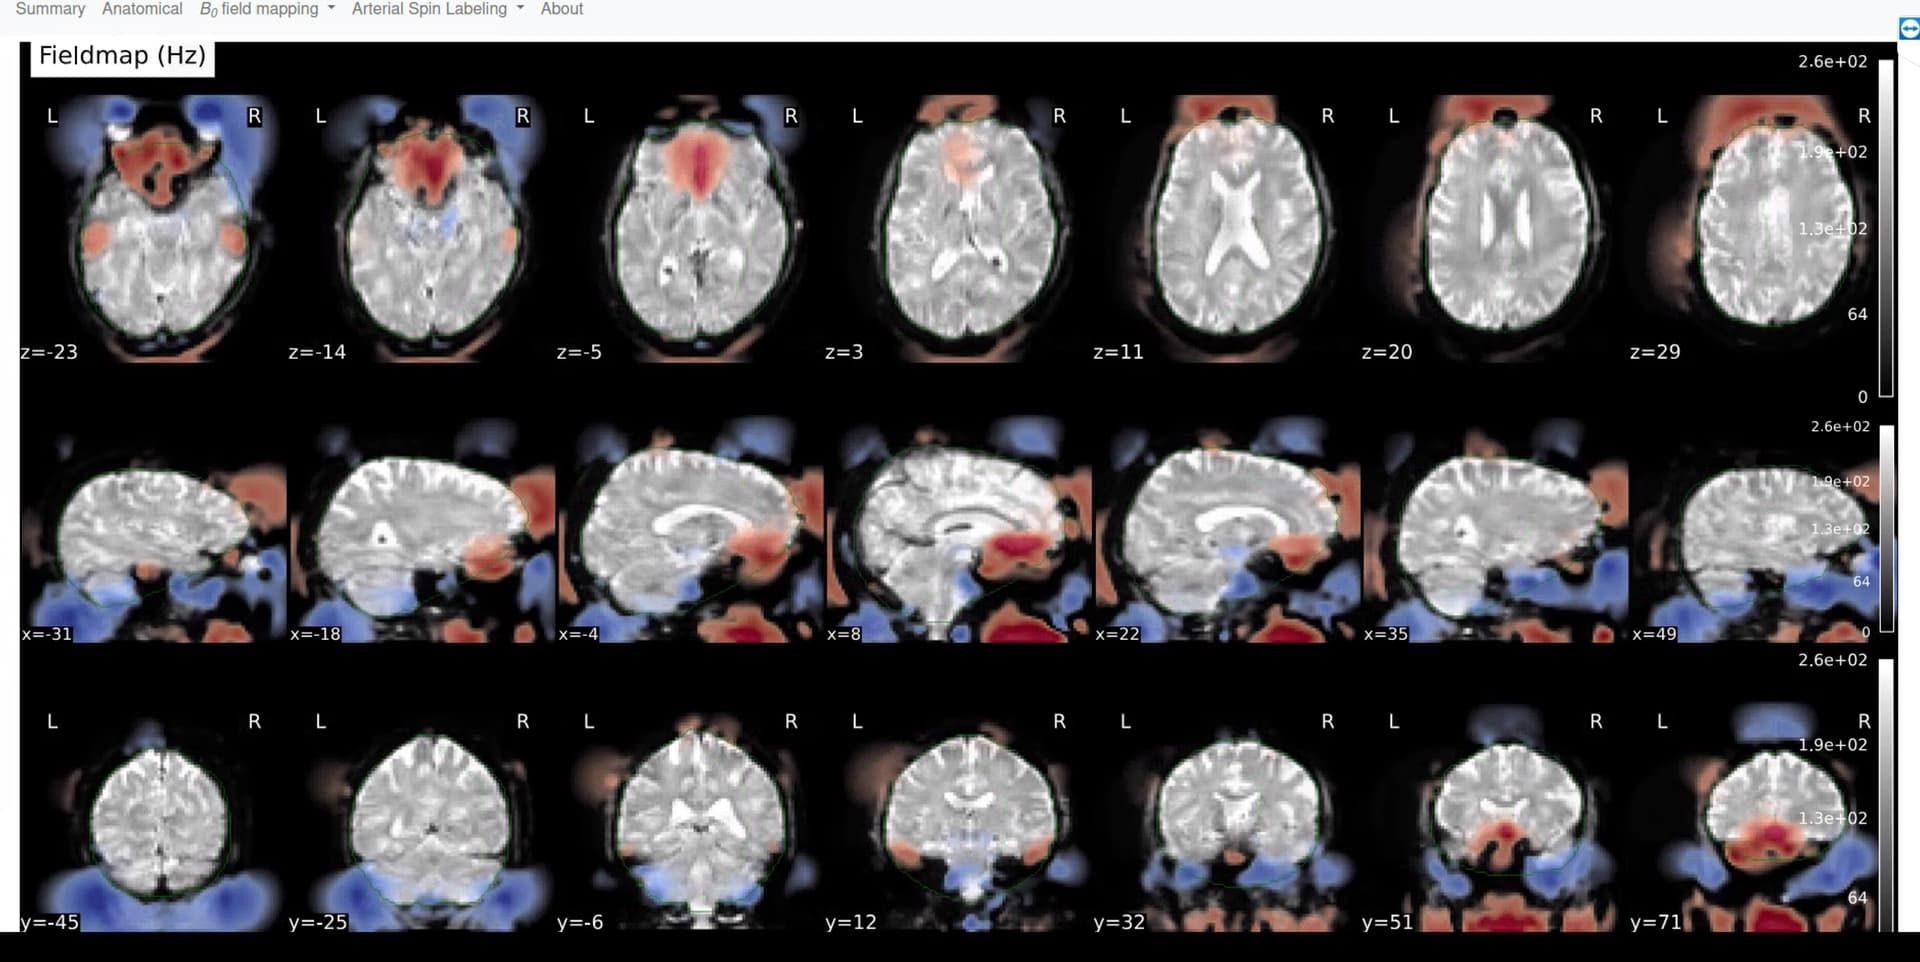

I am using aslprep version 26.0 to preprocess pCASL data (Siemens) and am having a bit of trouble. The program does not seem to recognize the fieldmaps.

Screenshots / relevant information:

We use one m0 and one flipped m0 scan for both runs, per session.

For each subject, there is a /perf and /fmap folder. I can send screenshots of the fmap folder. (We also collect rsfMRI.) For more context, I previously had the MzerooPE_epi in the fMAP folder on its own, but since ASLprep did not seem to recognize this, I ran bidscoin again to obtain the AP and PA sbref files from the fMRI.

For the flipped M0 metadata (.json in the fmap folder), the ‘Intendedfor’ field points to the M0 in the perf folder